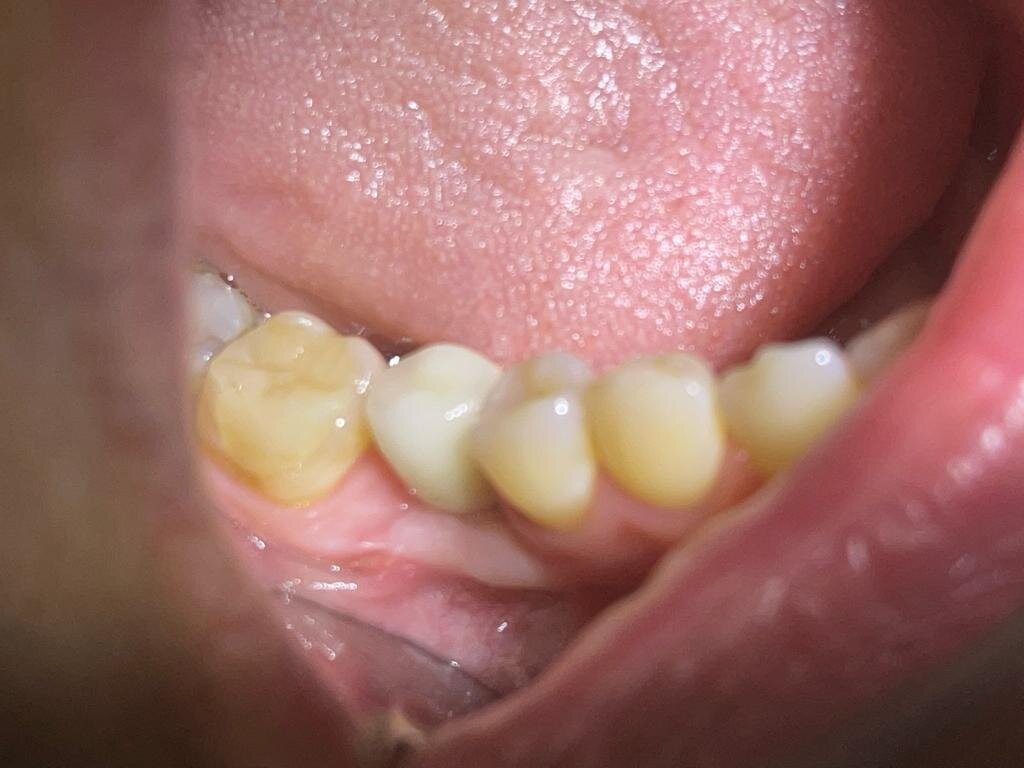

Но, что если у пациента есть десна, но ее толщина слишком маленькая. Это может привести к просвечиванию абатмента (вид синюшной десны) либо к нарушению эстетики (впалая десна).

Синюшная десна